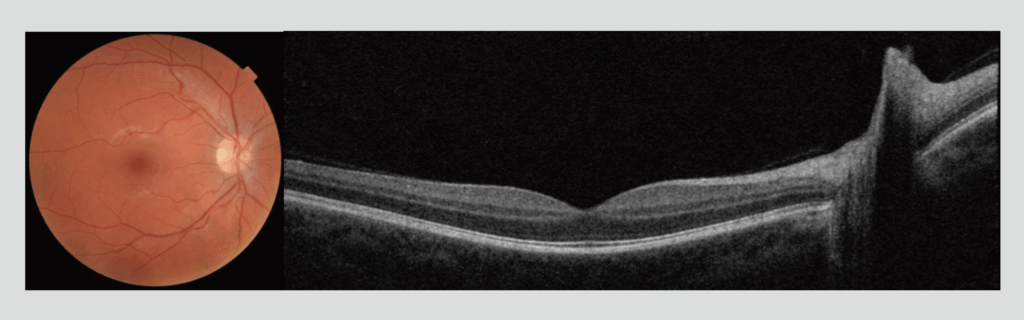

Several different OCT instruments are FDA approved and available for clinical use in the US. One OCT instrument that has been gaining popularity in comprehensive eye care settings is the Maestro2 (Topcon Healthcare, Tokyo, Japan). The Maestro2 captures a color fundus photograph and wide-field 12mm x 9mm OCT in a single scan to provide a comprehensive view and analysis of the macula, parapapillary and optic disc regions (Figure 1). Multi-modal examination. Examination of the macula and optic disc are essential for effective detection and management of glaucoma (Figure 3)*1,2,3 as well as for screening or managing of macular disease (Figure 4). A recent study conducted at the New England College of Optometry assessed the total chair time required to capture images of the macula and optic disc in 50 healthy eyes and 20 diseased eyes using the Maestro2.